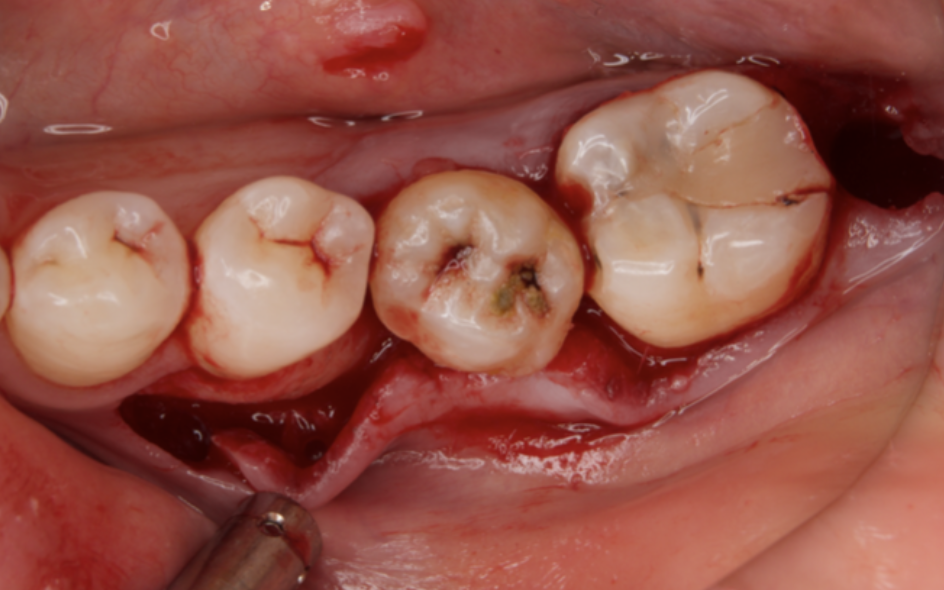

Figure 3.Preoperative intraoral findings. A metal crown was inserted at #46 and bleeding on probing during the periodontal pocket examination was noted.